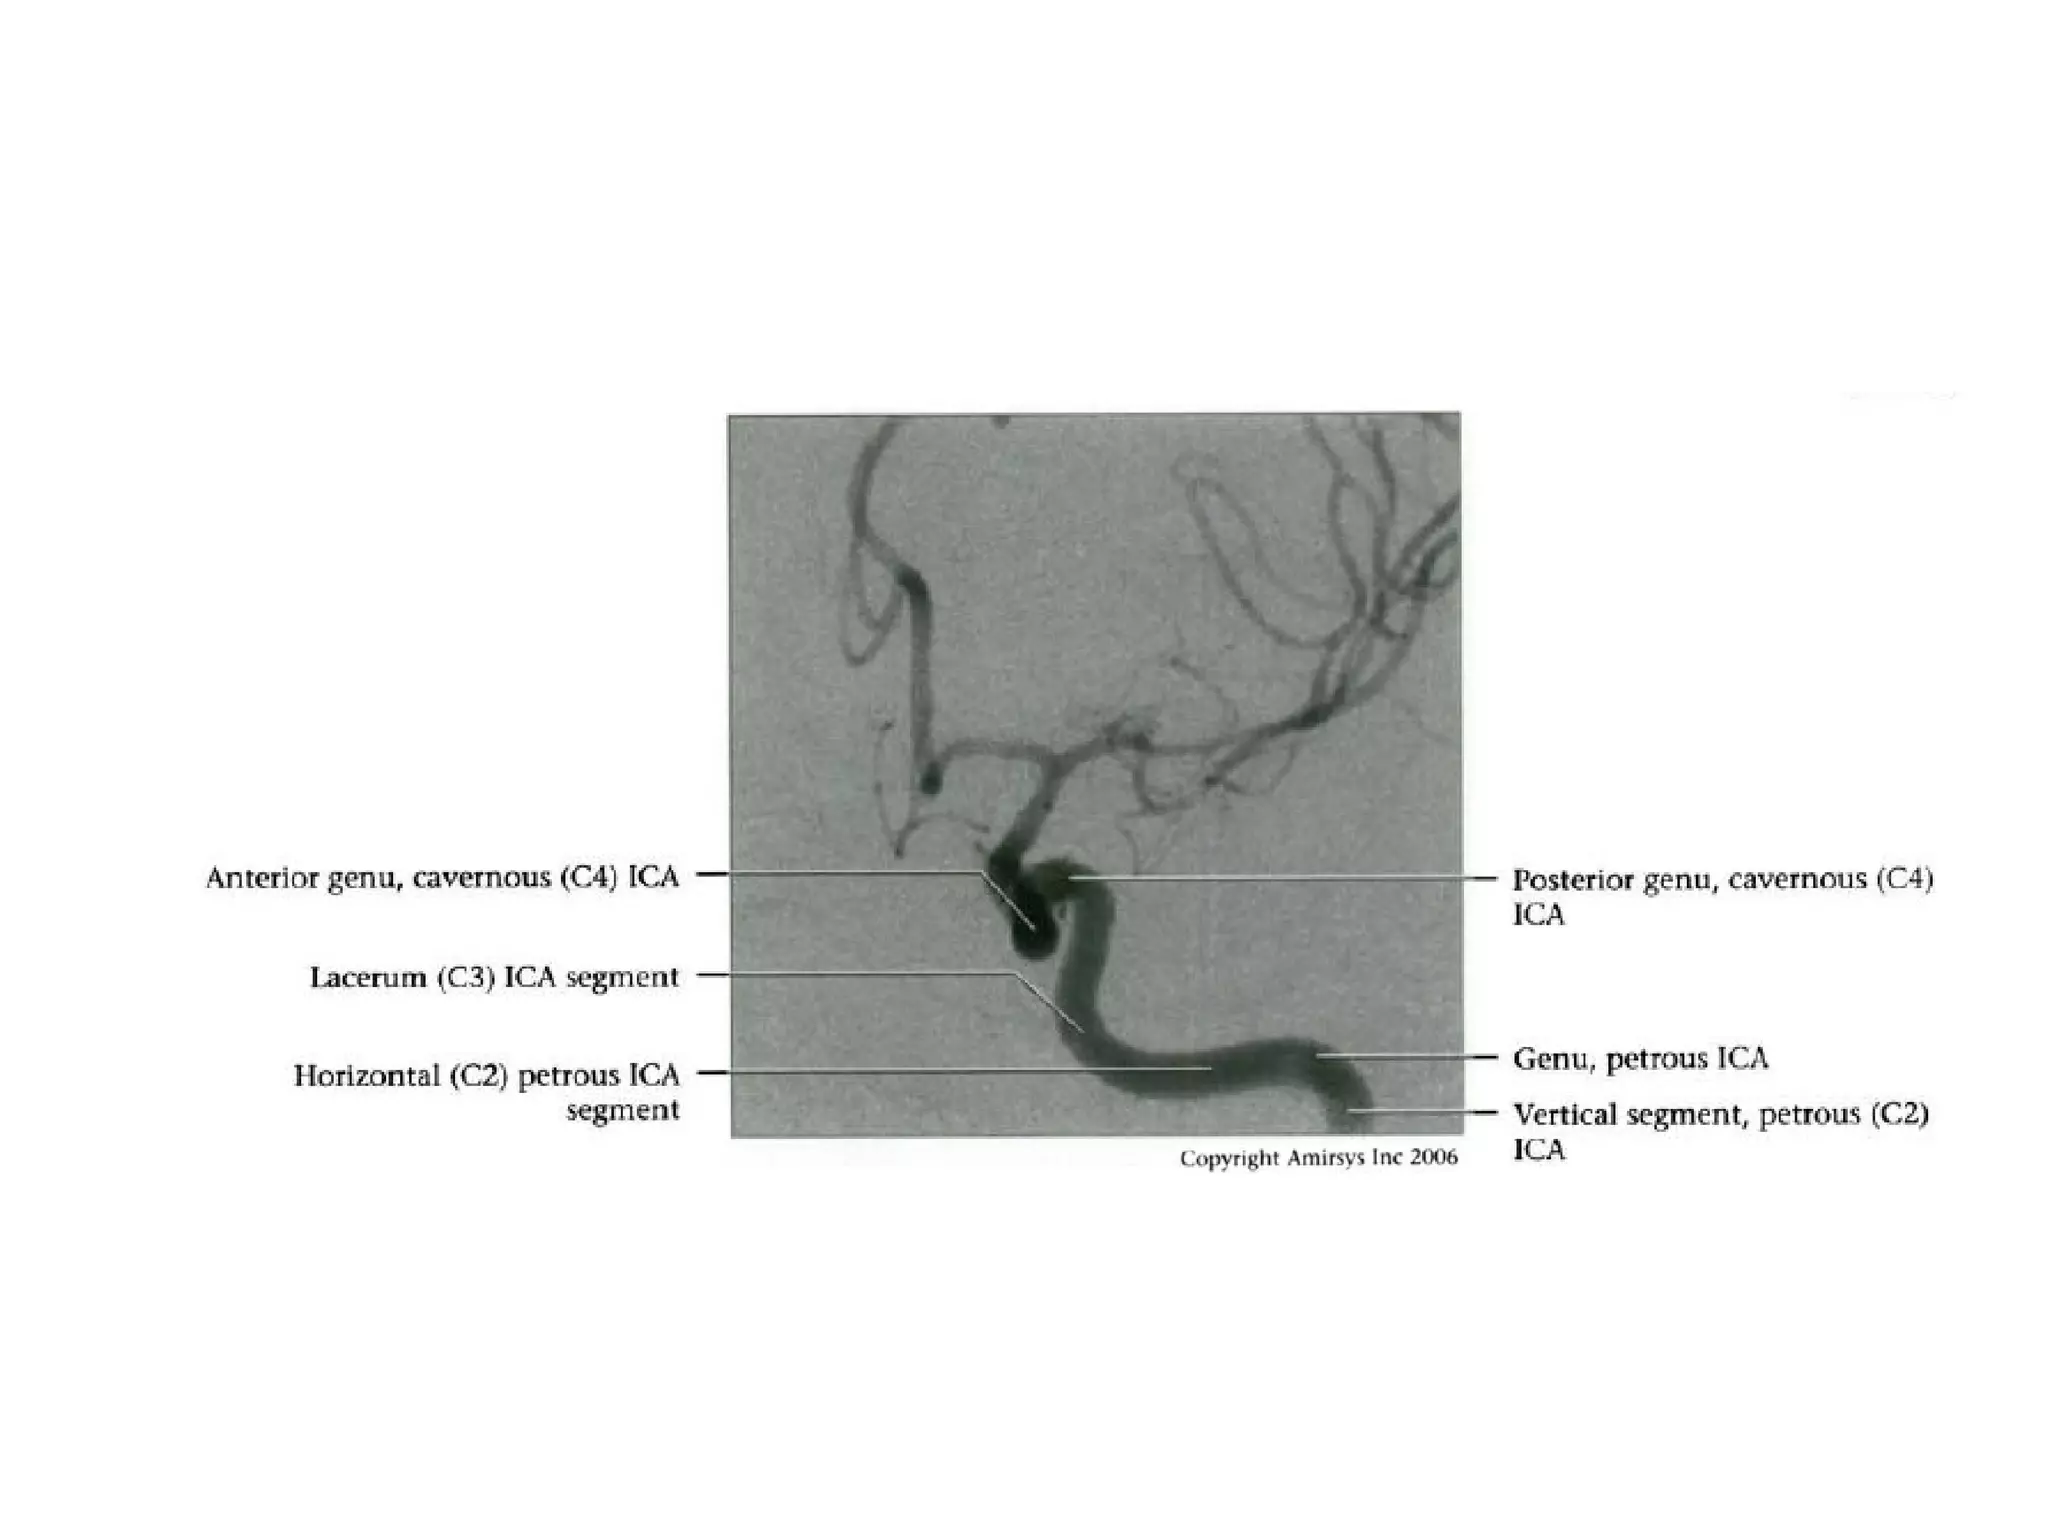

INTRACRANIAL INTERNAL

CAROTID ARTERY

Overview

• Complex course with several vertical /

horizontal segments, 3 genus (one

petrous, two cavernous)

• Six intracranial segments (Cervical lCA =

C1):

- Petrous (C2), Lacerum (C3),

Cavernous (C4), Clinoid (C5),

Ophthalmic (C6), Communicating (C7)

Lacerum (C3) segment

• Small segment that extends from petrous

apex above foramen lacerum, curving

upwards toward cavernous sinus

• Covered by trigeminal ganglion

• No branches

Cavernous (C4) segment

• Three subsegments joined by two genus (knees)

- Posterior vertical (ascending) portion

- Posterior (more medial) genu

- Horizontal segment

- Anterior (more lateral) genu

- Anterior vertical (subclinoid) segment